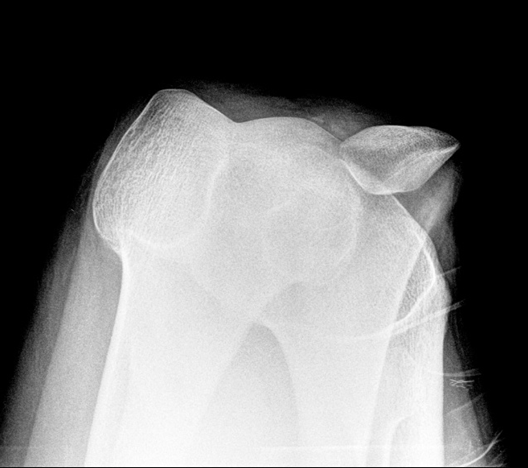

צילומי רנטגן: לכל חולה המגיע לבירור של אי יציבות של מפרק זה יש לבצע צילומם קדמיים- אחוריים (AP) נושאי משקל של שתי הברכיים, צילומים צידיים, וצילומים במנח- SKY (כיפוף 45 מעלות מעל קצה המיטה וזווית הקרן ב-30 מעלות כלפי מטה). צילומים קדמים-אחורים חשובים לשלילת שבר גרמי-סחוסי ((osteochondral, דלקת מפרקים ניוונית של המפרק שוקה-ירך ((osteoarthritis, גופים חופשיים במפרק וניתן לראות בהם בצורה הטובה ביותר מבנה קלוב ועקול. צילום צידי מאפשר הערכה של גובה הפיקה ודיספלזיה טרוכלארית. צילום SKY עוזר בהערכת הדיספלזיה הטרוכלארית. כך ניתן לראות האם קיימת הטייה של הפיקה, פריקה שלה או דיספלסיה של הטרוכלאה. זוויות ומדידות חשובות שניתן להפיק מצילומי רנטגן כוללים:

סימן CROSSING – הנקודה שבה הרצפה הטרוכלארית הקירבנית חוצה את הגבול הקדמי של כורמיז הירך המדיאלי והצידי בצילום צידי. ב96% מהחולים עם דיספלזיה טרוכלארית ניתן לראות סימן זה. ככל שנקודה זו רחיקנית יותר כך הדיספלזיה חמורה יותר.